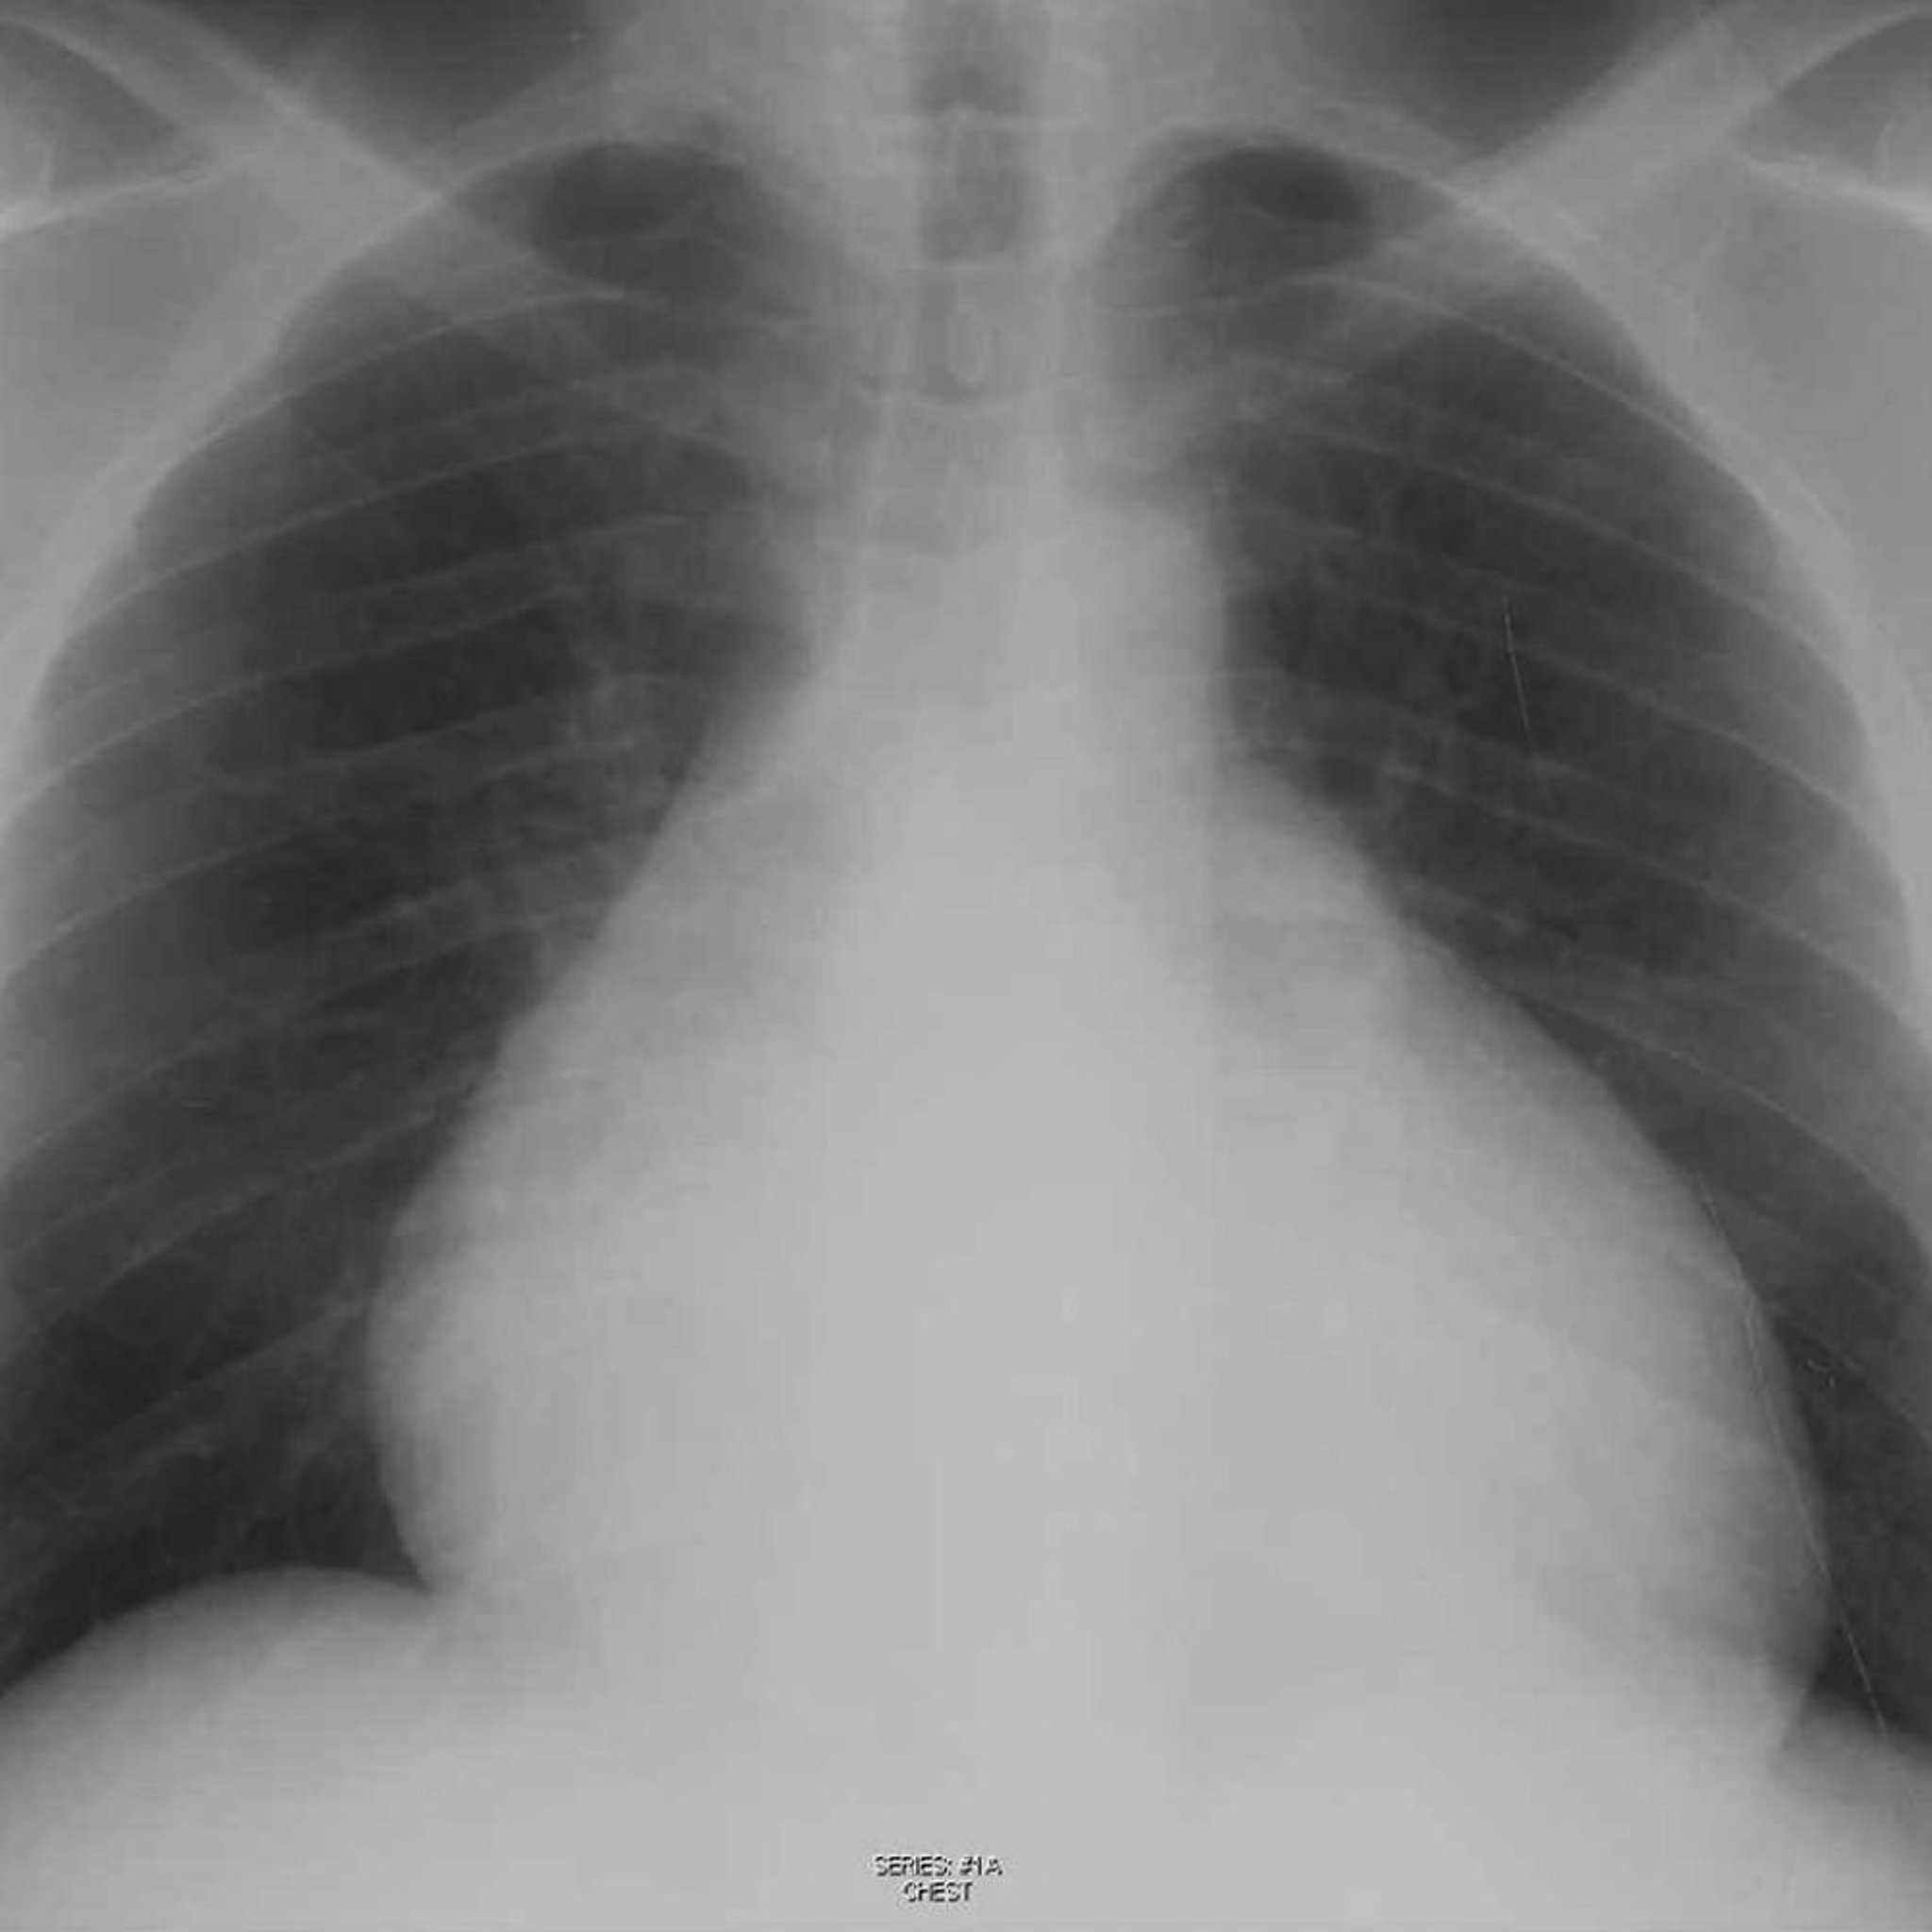

Chest Radiograph of a Patient with Pericardial Effusion

This radiograph shows enlarged cardiac silhouette in a patient with a pericardial effusion.